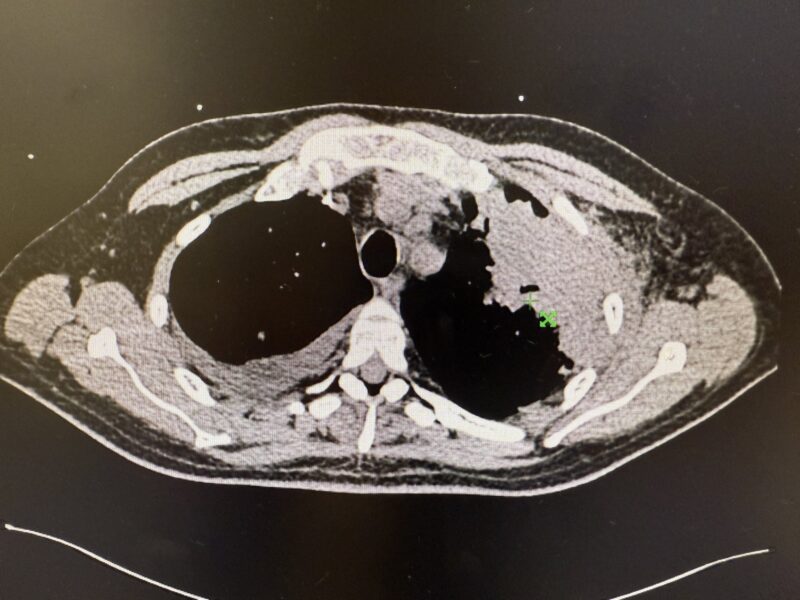

“41 yrs old with AML required re-induction due to residual disease at D14. Culture proven invasive aspergillosis refractory to Posaconazole.